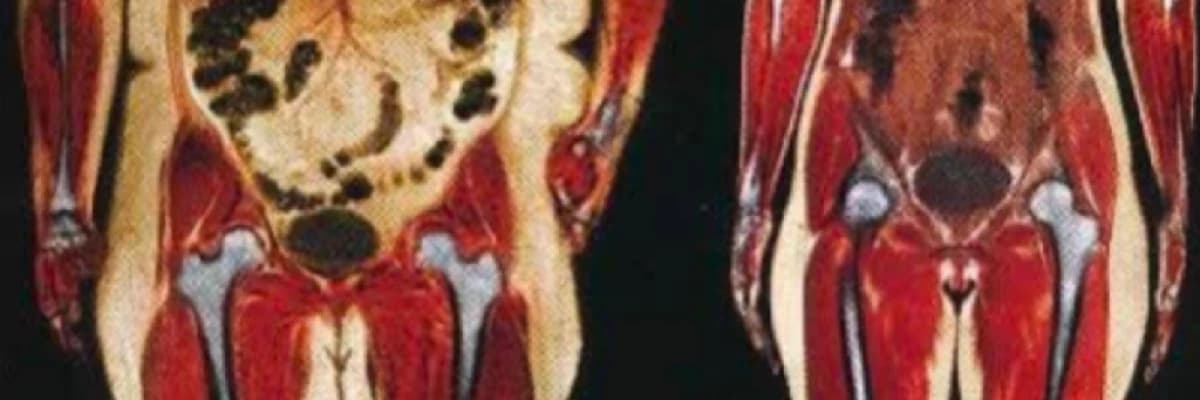

5. **Bilgisayarlı Tomografi (BT) veya Manyetik Rezonans Görüntüleme (MRG):** İleri vakalarda, iç yağlanma genellikle BT veya MRG gibi görüntüleme testleri ile doğrulanabilir. Ancak, bu testler genellikle iç yağlanma tespiti için rutin olarak kullanılmaz.